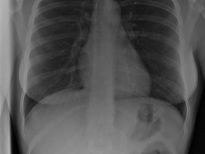

Bu röntgenler gerçek!